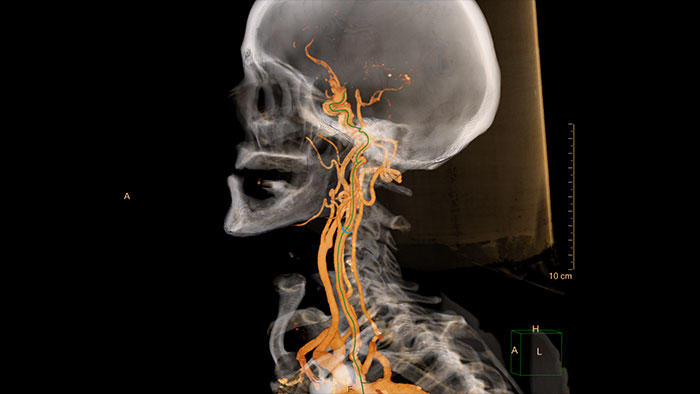

Comprehensive vascular analysis planning

Designed to examine and quantify different types of vascular lesions from CTA and MRA scans. It accommodates different modes of inspection, allows labeling different vascular lesions, and helps navigating through multiple findings. Demonstrated to reduce the post-processing time by 50% when compared to manual Head & Neck CT angiography (CTA) analysis*.

* Ardley N et al. Efficacy of a new post processing workflow for CTA head and neck. ECR 2013 / C-1760.